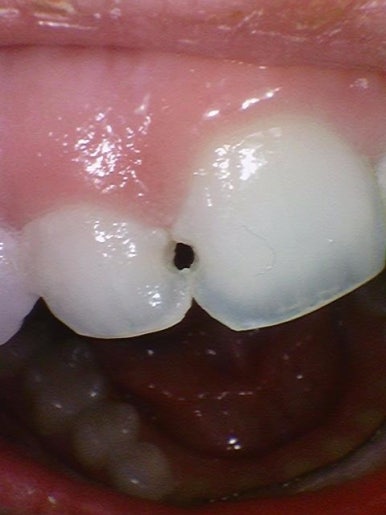

앞니사이 충치치료